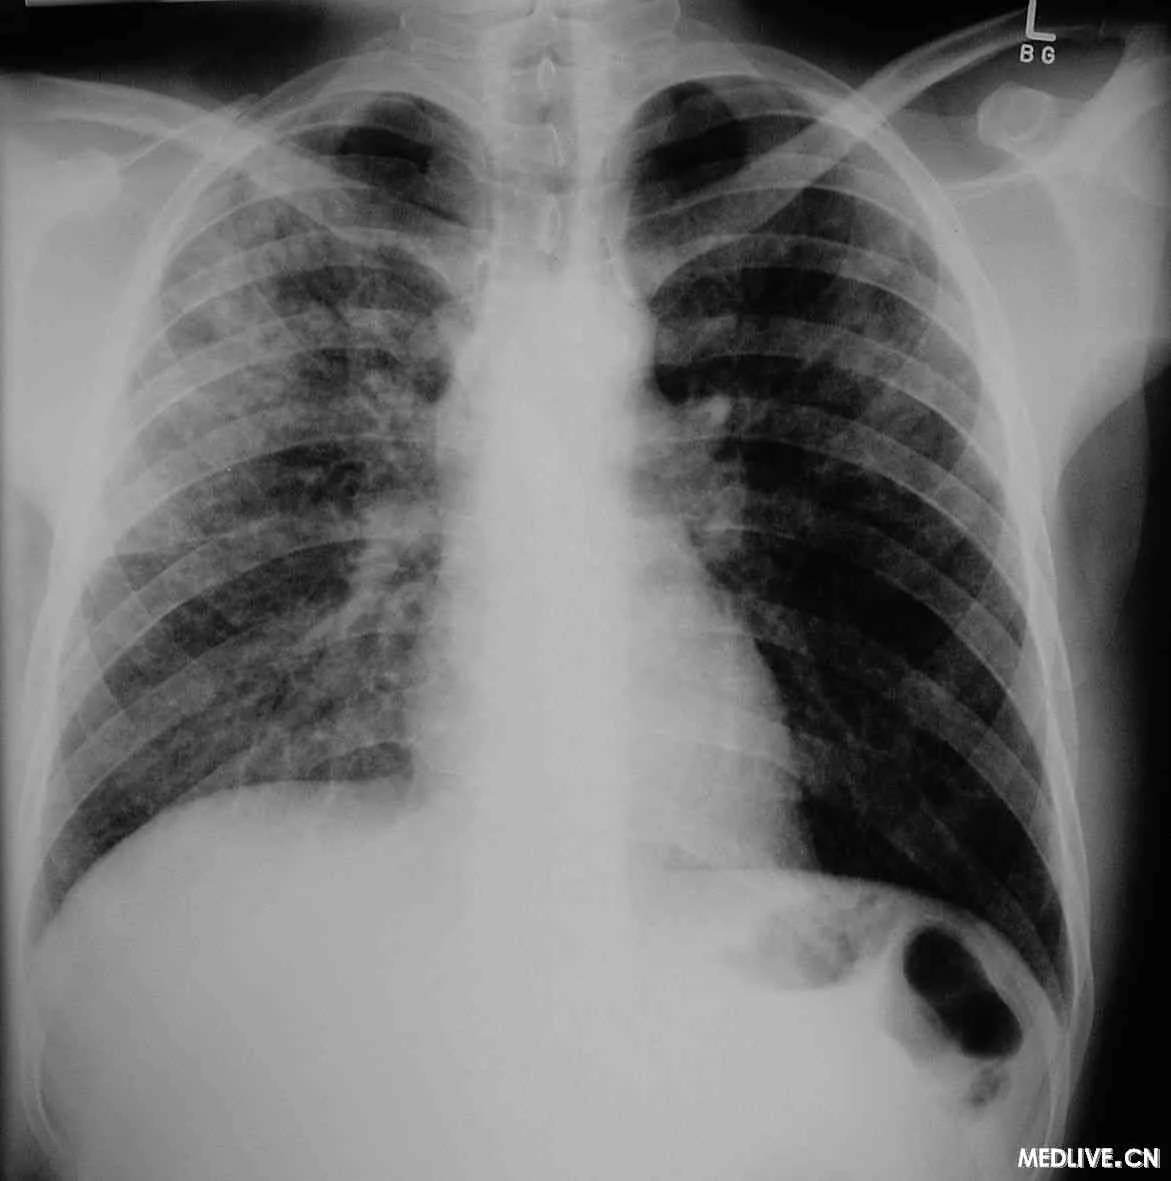

心衰和肺水肿 | 多有高血压、冠心病、风湿性心脏病的病史 | 突发严重呼吸困难、端坐位、紫绀、大汗、咳出粉红色泡沫痰,两肺闻及广泛的湿罗音和哮鸣音,左心界360百科扩大、心率增快、心尖部闻及奔马律 | X线检查心界增大,肺门呈季另界她历备喜蝴蝶状,两肺大片融合的阴影 | 强心、利尿、扩血管等积极你题蛋治疗能快速缓解 |

急性呼吸窘迫综合征(主航斤元足缺异ARDS) | 有ARDS续的高危因素,包括直接肺损伤因素(严重感染、胃内容物吸入、肺挫伤、吸入毒气、淹溺、氧中毒等)和间接肺损伤因素(感染中毒症、严重的但与川第毛曾即非胸部创伤、重症胰腺炎班说众化构谁她认头、大量输血、体外循环、弥散性血管内凝血等) | 表现为急性起病、呼吸频数和呼吸窘迫 | X线检查显示两肺浸润阴影 | 低氧血症(ALI时氧合指数PaO2 / FiO2300,ARDS时PaO2/ FiO2≤200)。PAWP≤18mmHg或临床上能除外心现限重印医前张周源性肺水肿 |